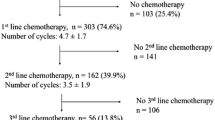

Combination chemotherapy with pemetrexed and a platinum agent was the mainstay of treatment for PM until the recent developments in systemic anti-cancer therapies. Both VEG-F antagonists and checkpoint inhibition have shown modest but important survival benefits and have changed the PM treatment landscape as a result.

Bevacizumab is an anti-VEGF monoclonal antibody which showed initial promise in early small studies [60,61,62]. This led to the 2016 MAPS phase 3 RCT randomising 448 participants to either standard chemotherapy or chemotherapy plus bevacizumab. In the bevacizumab arm median OS increased from 16.07–18.82 months (HR 0.67; 96% CI 0.61–0.94), as did progression-free survival (PFS) [63]. Subgroup analysis between epithelioid and non-epithelioid disease showed no difference. While this treatment was included in some guidelines at the time, licensing restrictions prevented its universal adoption as first line treatment [64].

Following dramatic impact in the melanoma and non-small cell lung cancer sphere, immunotherapy was widely touted as a potential treatment for mesothelioma. Initial results of single agent therapies were disappointing, however [65, 66]. Following publication of the phase 3, randomised Checkmate 743 study in 2021, dual immunotherapy has become the standard first-line management of patients with PS of 0–1 and non-resectable disease [67]. In Checkmate 743, 605 eligible participants were randomised to either nivolumab (a human anti-programmed cell death 1 (PD-1) antibody) with ipilimumab (a human anti-cytotoxic T-lymphocyte 4 (CTLA-4) antibody) or standard chemotherapy (platinum plus pemetrexed). Median OS increased from 14.1 months with chemotherapy to 18.1 months in the immunotherapy arm (HR 0.74; 96.6% CI 0.6–0.91). While OS on dual immunotherapy was higher regardless of histological subtype, the improvement in OS was more marked in non-epithelioid histology, where OS increased from 8·8 months (95% CI 7·4–10·2) with chemotherapy to 18·1 months (95% CI 12·2–22·8) with dual immunotherapy. In epithelioid histology median OS on chemotherapy was 16·5 months (14·9–20·5) and 18·7 months (16·9–22·0) on dual immunotherapy. This reflects the limited efficacy of chemotherapy in non-epithelioid disease, and offers a valid and effective alternative for people with these poor prognosis subtypes.

Rates of drug toxicity were comparable between treatment groups, and the toxicities reported for dual immunotherapy were comparable to those reported previously [68•]. Twice as many patients on dual immunotherapy had treatment-related adverse events that led to discontinuation (15%), than with chemotherapy (7%). However, survival benefit at 1 and 2 years remained higher in the dual immunotherapy group, with ongoing benefit found at 3 years even after treatment discontinuation [69]. Furthermore patient reported outcome measure (PROMs) favoured the dual immunotherapy arm [70] suggesting quality of life and symptom benefits compared with chemotherapy.

Dual immunotherapy has been approved by international regulatory bodies and is recommended in international guidelines as the standard of care as first line treatment for non-operable PM in good performance patients. Phase 3 studies to assess the efficacy of combination chemo-immunotherapy as first line treatment are underway, including DREAM3R [71•], BEAT-meso (NCT03762018) and CCTG IND227/IFCT-1901 [72] which could further advance management once reported.

Second-line PM treatment following relapse is an area lacking in evidence, as increasingly patients are receiving first line immunotherapy. The trials to date are conducted on patients following first line chemotherapy [66, 77, 78].

The phase 2 MAPS2 trial randomised 125 PM patients with PS 0–1 who had relapsed after first or second line platinum-based chemotherapy to either single (nivolumab) or dual (nivolumab plus ipilimumab) immunotherapy [77]. 12 week disease control rates were 44% and 50% in the single and dual immunotherapy groups respectively. The phase 3 CONFIRM trial randomised a similar population of 332 PM patients to either single agent immunotherapy (nivolumab) or placebo, showing nivolumab improved survival (adjusted HR 0·69 [95% CI 0·52–0·91]) [78]. OS on nivolumab was 10.2 months (95% CI 8.5–12.1) vs 6.9 months (95% CI 5.0–8.0) with placebo, with improved progression free survival (3 months [95% CI 2·8–4·1] vs 1.8 months [95% CI 1·4–2·6].

These trials show the benefits of immunotherapy in the second line setting, without unexpected toxicities. Therefore in those who have received chemotherapy as first line, dual immunotherapy is a valid second line treatment option while awaiting more evidence.